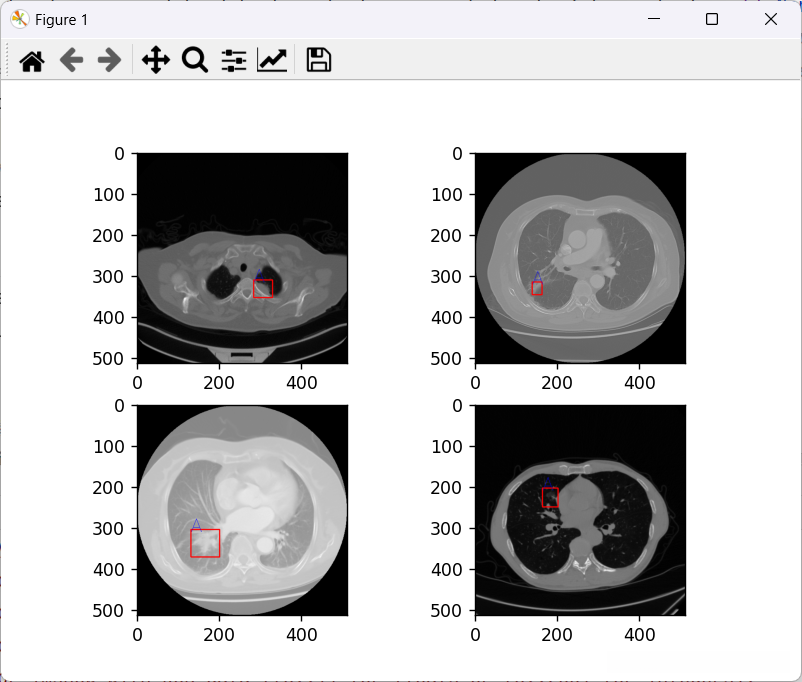

如图为数据集展示,其中被选中的部分就是病状

4.2 可视化

测试代码

#load a batch data + 可视化

img,label = next(iter(testLoader))

draw_bounding_box(img,label)

显示结果: